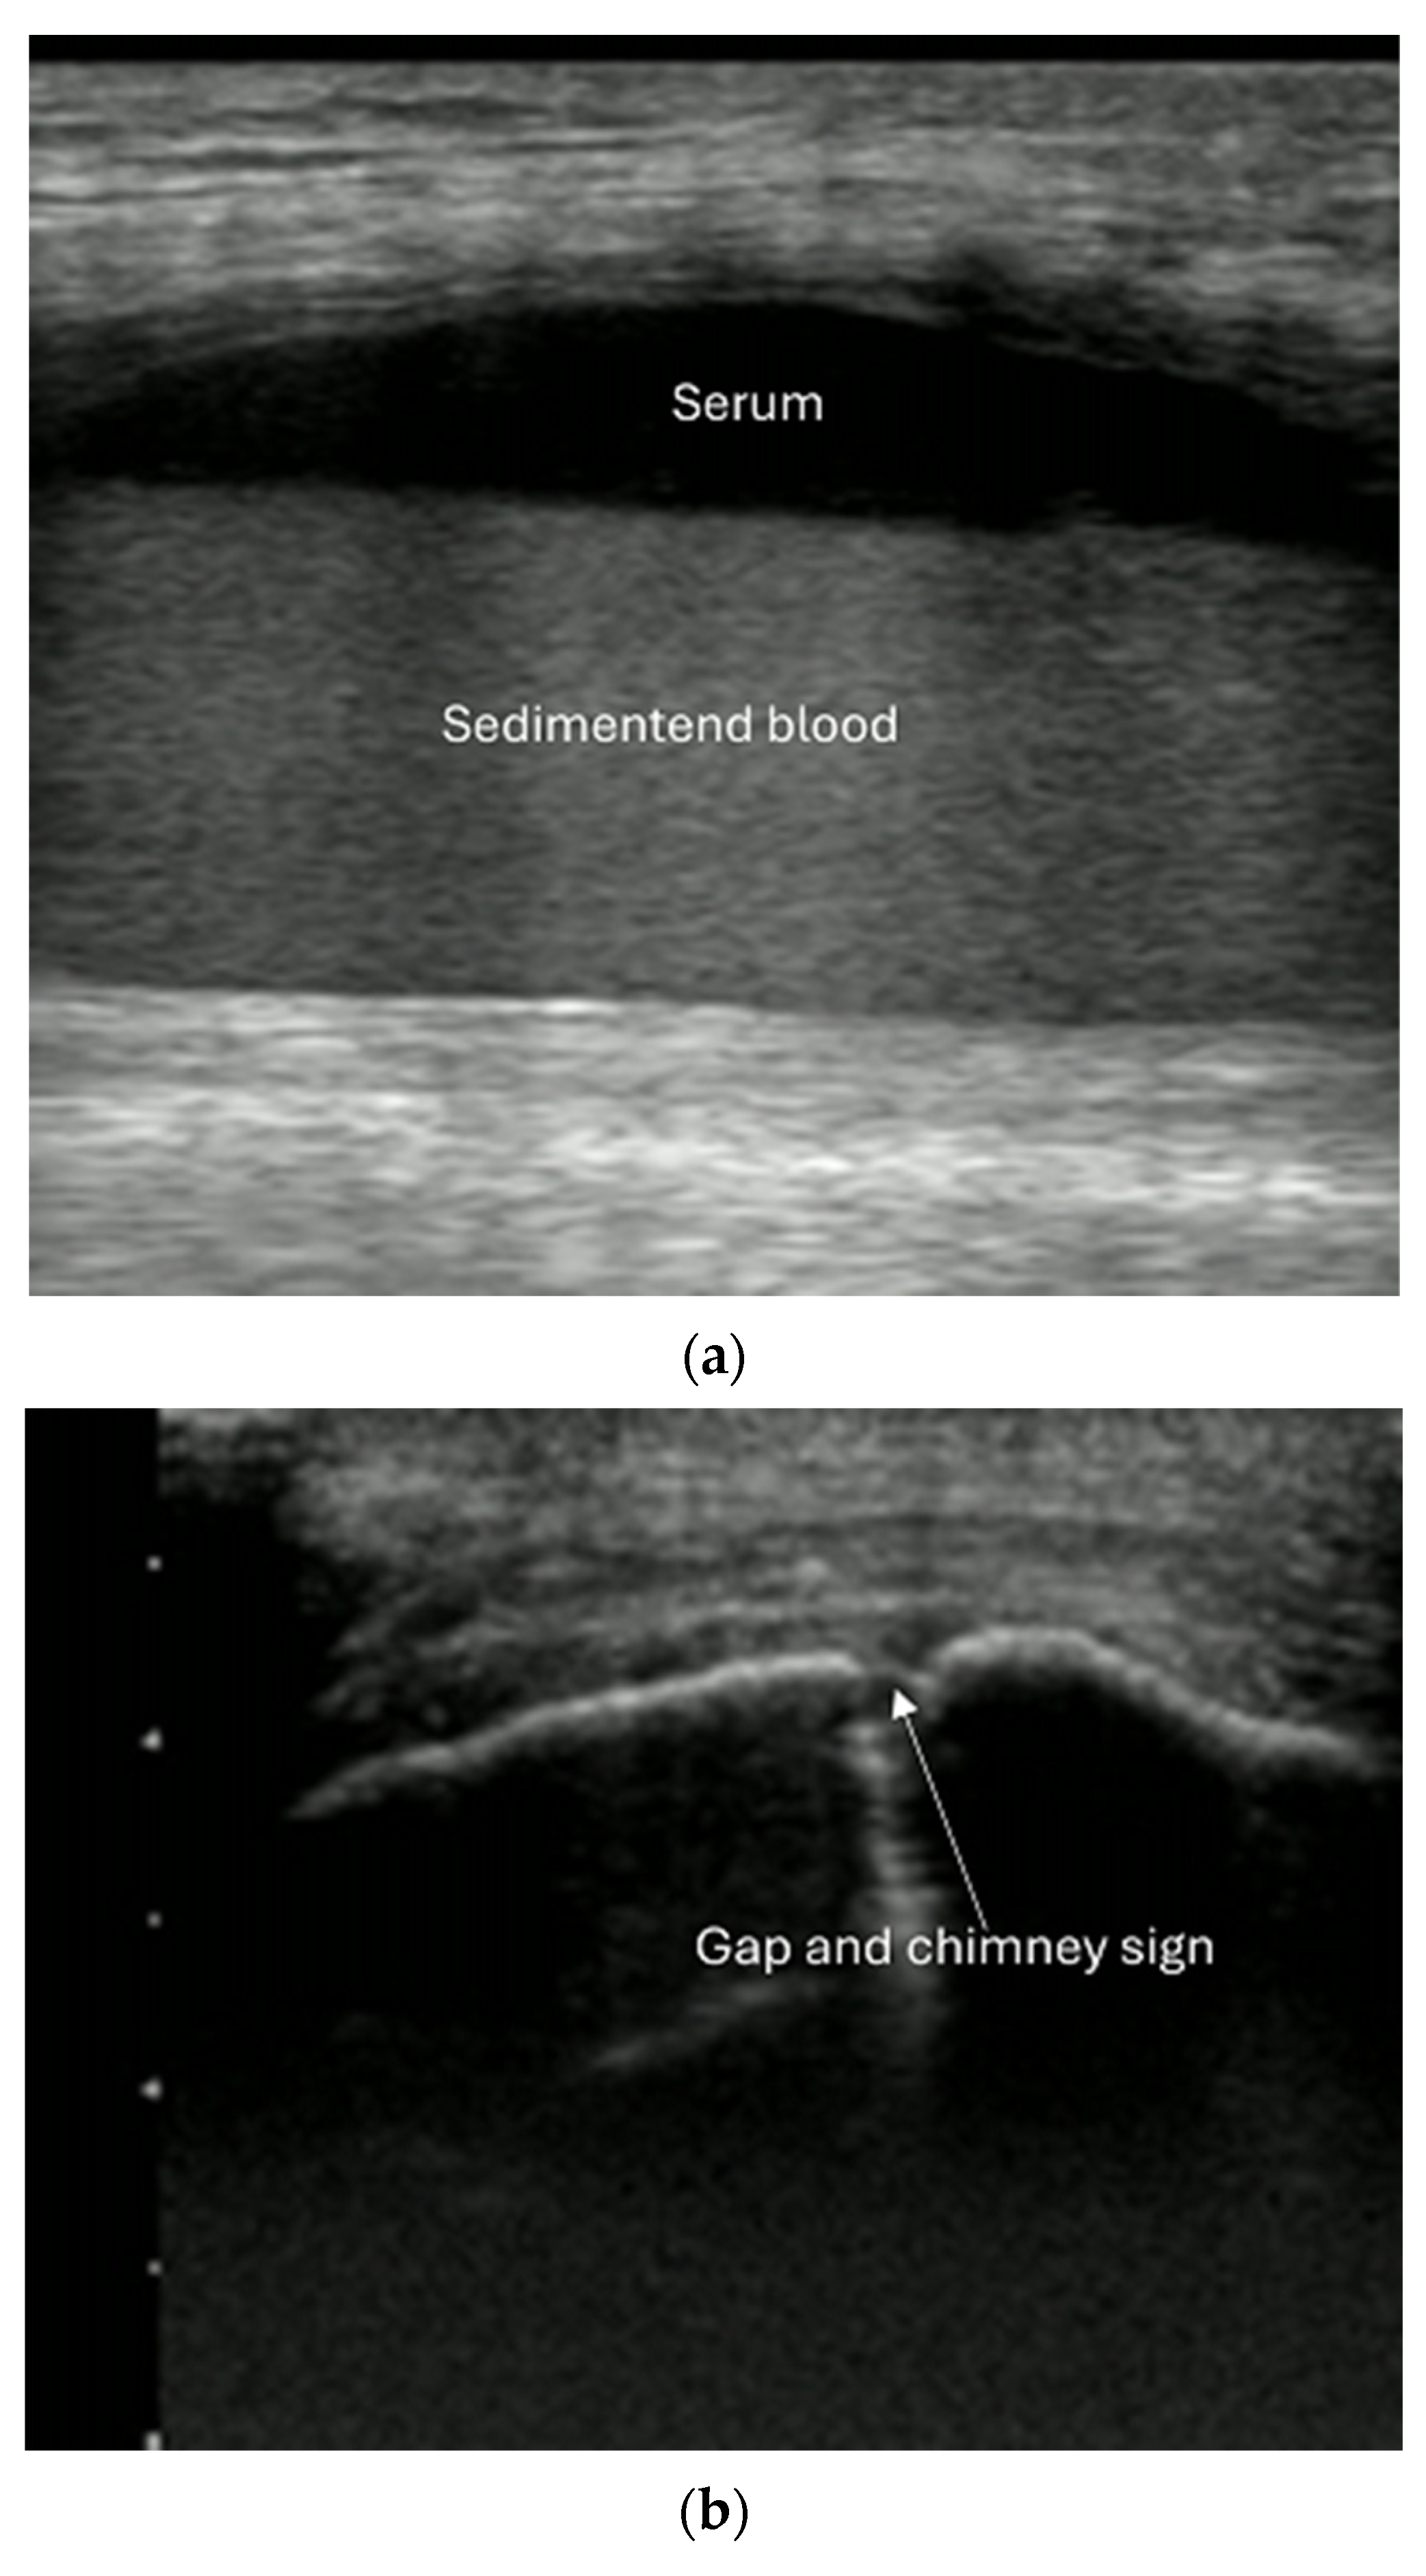

4.2. Sonoanatomy of Fractures [Figure 5, Figure 6, Figure 7 and Figure 8]

- Reverberation artifacts within or adjacent to the fracture gap (also known as the “chimney sign”): these repetitive echoes are caused by ultrasound waves reflecting off the fracture surfaces.

- Local hematoma or soft tissue edema: fluid collections or increased echogenicity near the fracture site indicating bleeding and inflammation.

- Joint effusion and liphemarthrosis: fluid accumulation within a joint, sometimes containing fat droplets, which often indicates an intra-articular fracture.